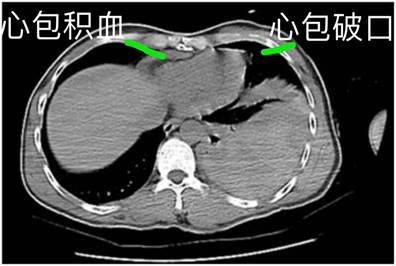

吴主任带领其胸心外科团队,快速用腔镜给予其左侧胸腔探查发现,文先生左上肺部分裂伤,心包裂伤,左心室近心尖处有一个约75px的横行刀刺裂口,裂口宽约37.5px深达心内膜,未见到明显活动大出血。迅速清理干净文先生胸腔和心包腔内的积血血块,正准备实施左侧心室刀刺裂口修补缝合。但是,突然左侧心室刀刺穿透伤口堵塞的血凝块脱落,大量活动出血并伤口大,微创手术缝合修补左侧心室刀刺穿透伤口变得非常困难,必须立即开胸“补心”。